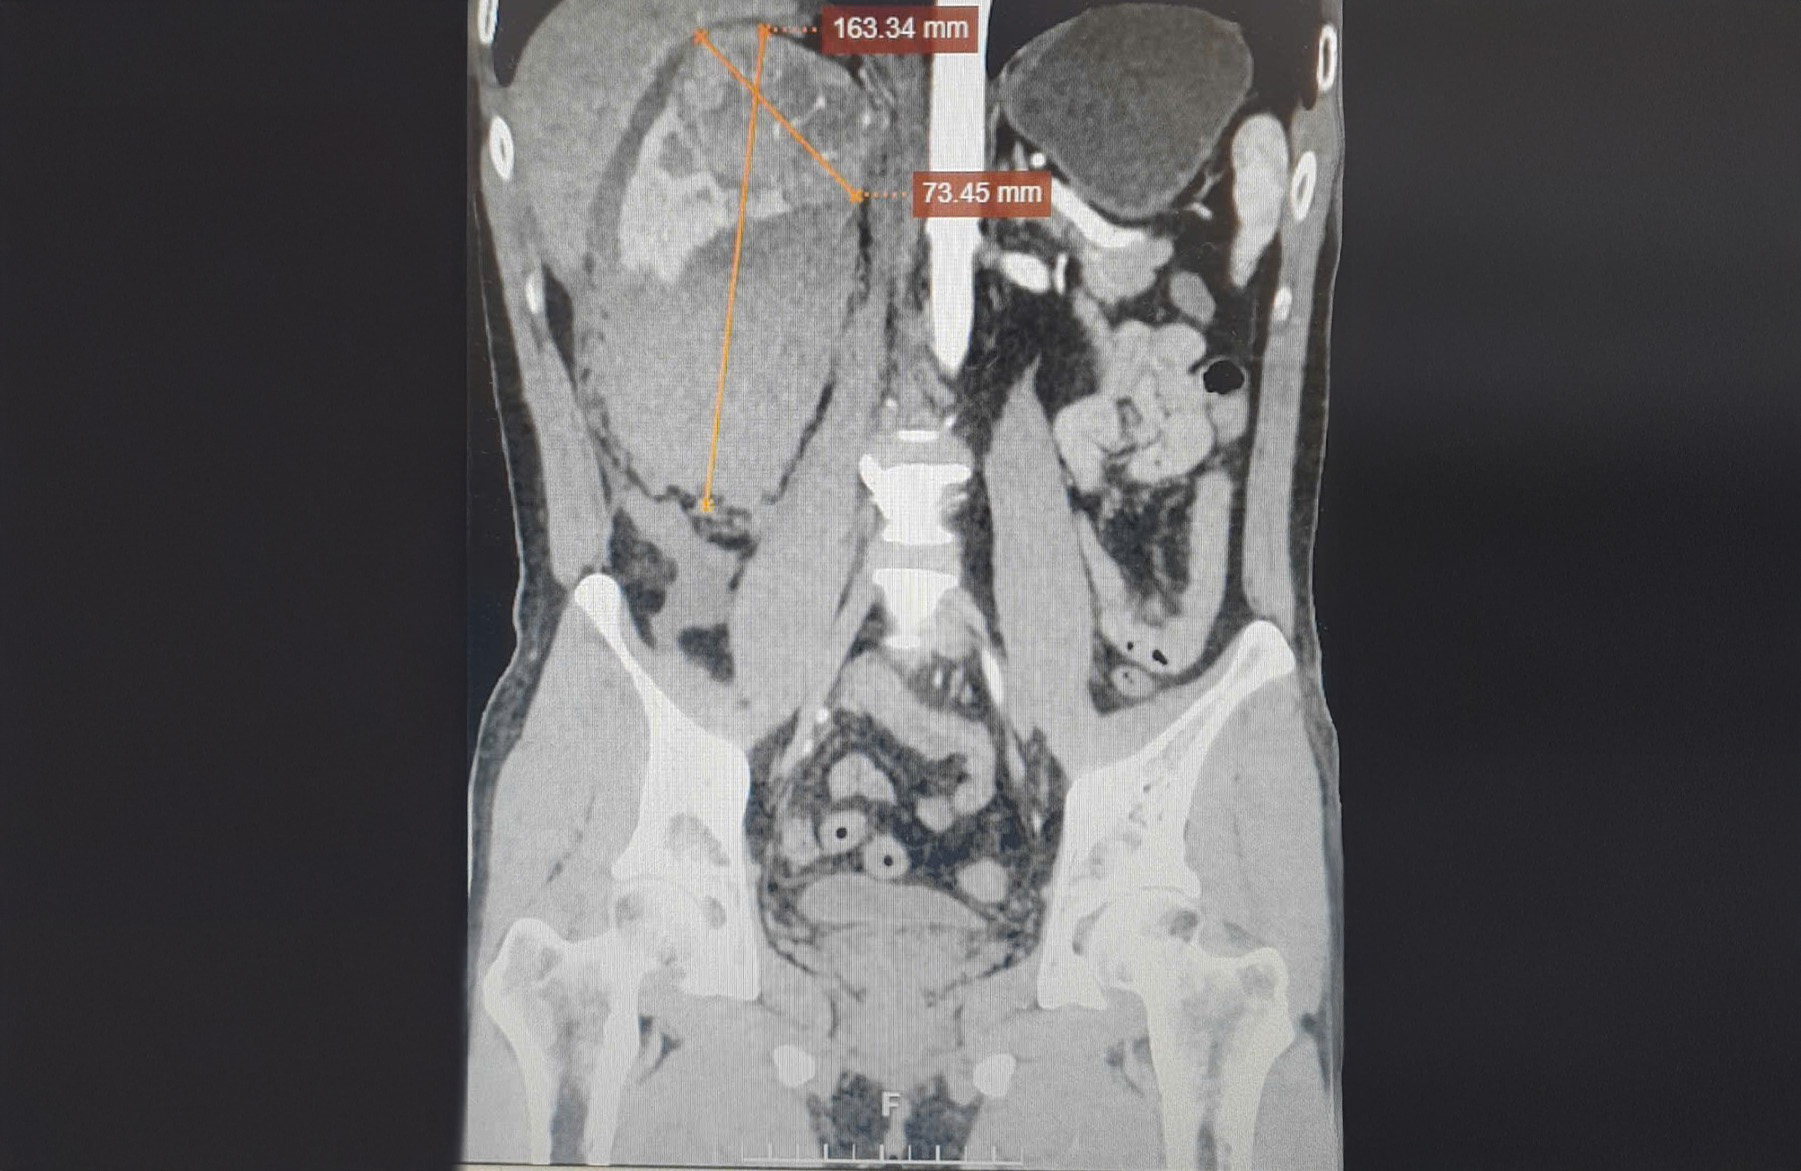

Nam's 8 cm tumor in the right kidney was bleeding. *Photo: Tam Anh General Hospital* |

Due to the tumor's size, kidney-sparing surgery was not possible. The doctors decided on a laparoscopic right nephrectomy, removing the ruptured kidney tumor and completely dissecting the hematoma around the kidney, to avoid the risk of cancer cell spread if it were malignant. The specimen removed from the patient's body was sent for pathological analysis, and one week later, the results confirmed clear cell renal cell carcinoma (ccRCC), stage T2a.